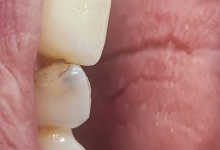

In acest timp are loc procesul de integrare in formatiunea osoasa. Succesul integrarii implantare este dat de catre formarea unei cantitati suficiente de celule osoase in jurul implantului dentar. In functie de necesitatile functionale sau estetice ale pacientului, urmeaza etapa protetica de realizare a lucrarilor de ceramica sau zirconiu. Implantul dentar este foarte important deoarece oasele maxilare se resorb, iar structura fetei incepe sa se modifice. In lipsa dintilor, atat masticatia cat si estetica au de suferit. O igiena necorespunzatoare, fumatul, bruxismul, etc., sunt factori de risc care duc la deteriorarea implantului. In perioada urmatoare dieta pacientului trebuie sa fie moale si la temperatura camerei.